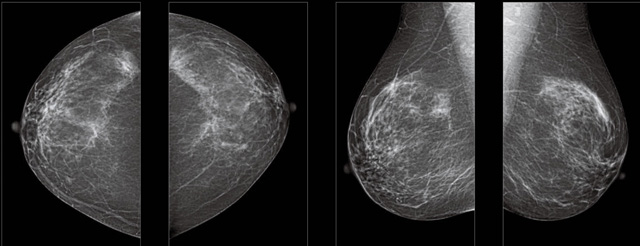

采用影像檢查技術來發現疑似特定病檢查跟人群的普查。一到兩年進行一次X光線的乳腺檢查。記過是C或者D型,可以加上B超協同。還可以一年一次核磁共振MRI檢查。70歲以上的女性認為絕經的女性是比較安全的。實際上也有乳腺癌的風險。65歲以上風險也很大。也是需要進行機會性篩查。

2,乳房自檢在發現有異常情況下借助科學影像乳腺秋葵视频APP下载安装檢查,進一步明確診斷,可以檢查到臨床觸摸不到的腫塊的早期乳腺癌。乳腺DR的檢查早期乳腺癌的診斷率更高。鑒別惡性、良性腫瘤的準確率可以有90%以上。可以讓乳腺癌死亡率降低很多。乳腺DR還可以跟鉬靶X光射線檢查配合,無毒無害無輻射。還可以鑒別囊乳腺增生等其他乳腺疾病。